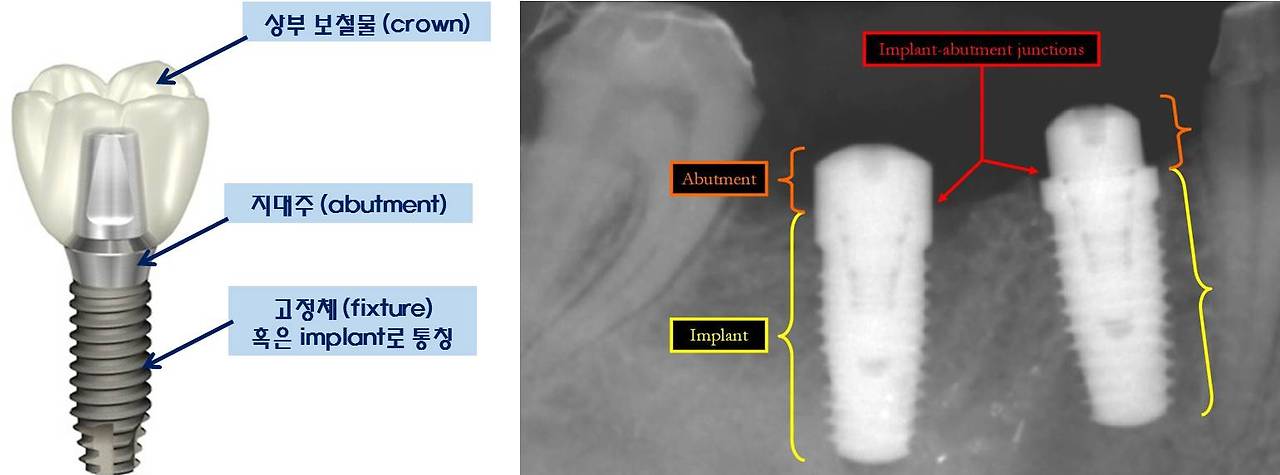

임플란트 구성요소에 관한 용어설명을 미리 하는 것이 독자의 이해를 도울 수 있을 것 같다. 임플란트는 크게 고정체(fixture), 지대주(abutment), 상부 보철물(crown)로 구성된다. 골유착과 관련된 것은 고정체로, 앞으로 자주 언급될 요소이다.

임플란트 구성